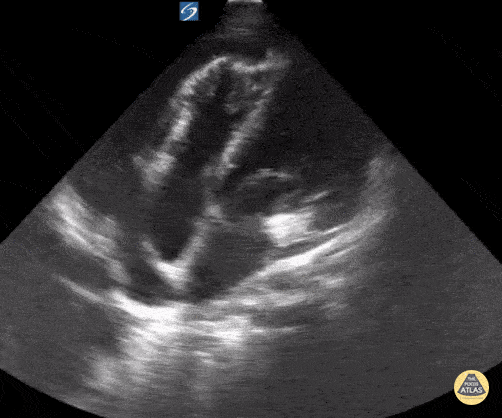

15 year old with lupus presents with chest pain and shortness of breath. POCUS shows a pericardial effusion with tamponade. Contributor: Kathryn Pade, MD, Rady Children's Hospital San Diego